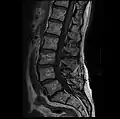

MRI lumbar spine with degeneration, post-hemilaminectomy L4-5 (sagittal T2 FRFSE)

MRI lumbar spine with degeneration, post-hemilaminectomy L4-5 (sagittal T1 FSE)

MRI lumbar spine with degeneration, post-hemilaminectomy L4-5 (sagittal FAST STIR)- MRI lumbar spine post-hemilaminectomy (sagittal T2 FRFSE)